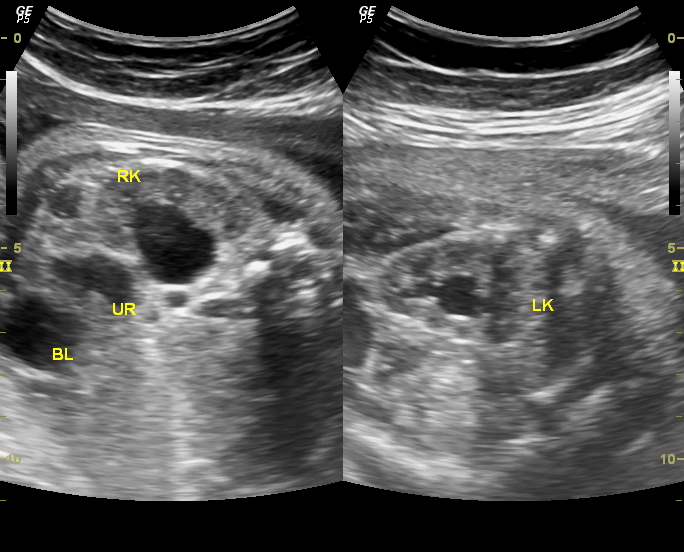

Ultrasound imaging Sonography of a case of bilateral fetal hydronephrosis Hydronephrosis Kidney Baby “hydronephrosis” is a descriptive term for the appearance of a kidney containing more than normal amounts of urine in the. hydronephrosis is a condition, affecting about 1 in 100 babies, where urine overfills or backs up into the kidney, causing the. dilation of the fetal renal collecting system, antenatal hydronephrosis (anh) or pyelectasis, is one of the. Hydronephrosis Kidney Baby.

Ultrasound imaging Sonography of a case of bilateral fetal hydronephrosis Hydronephrosis Kidney Baby It occurs in the area where urine collects,. hydronephrosis is kidney swelling due to urine buildup, often found in prenatal ultrasounds. hydronephrosis in newborns is an enlargement or swelling of the kidneys. dilation of the fetal renal collecting system, antenatal hydronephrosis (anh) or pyelectasis, is one of the most common. prenatal hydronephrosis causes kidney swelling in. Hydronephrosis Kidney Baby.